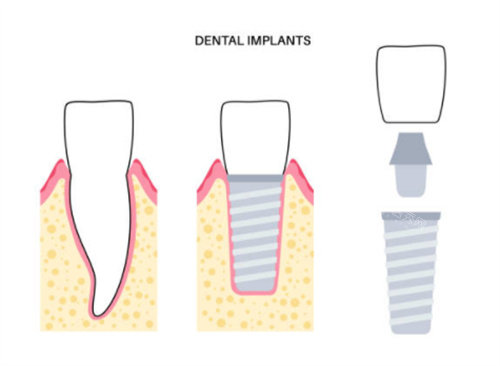

登腾种植体在临床应用中表现出几个显著特点。首先,其双螺纹设计提供了较好的初期稳定性,这对于骨条件良好的患者来说是一个优势。这种设计使得种植体在植入后能够更快地与骨组织结合,为后续修复奠定基础。

在产品线方面,登腾提供了多个系列选择,包括SuperLine、SimpleLineII和Implantium等。这些不同系列可以满足单颗牙缺失、多颗牙缺失乃至全口缺失等多种情况。特别是对于牙槽骨高度不足或需要即刻种植的患者,登腾的某些系列产品可能更为适用。

丽维思种植体在设计上更在意美学结果。其2.5mm直径的超窄径植体特别适合前牙区的修复,可以减少对邻牙的磨损。此外,该种植体的四级纯钛基台还配备了粉色仿龈瓷,能够更好地模拟天然牙龈的外观,提升整体美观度。

丽维思的另一个特点是其旋转停钻器设计,这一设计可以帮助医生更正确地控制种植深度,特别适合骨量不足或需要精细操作的情况。

骨量情况也是重要的考量因素。对于骨量不足的患者,登腾的短植体(5.5mm高度)或丽维思的特殊设计都可能是不错的选择。即刻种植的情况下,两款产品都有相应的解决方案,需要根据具体情况决定。